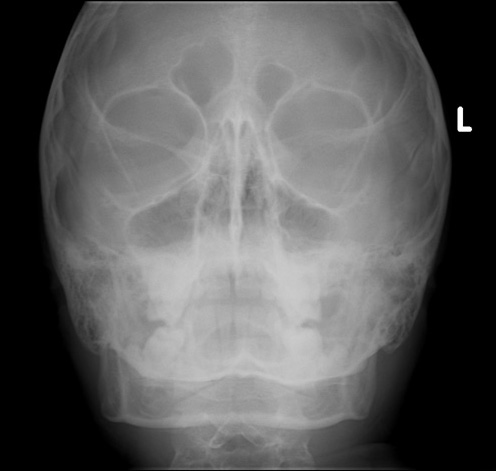

Identify the sinuses. Click the image for labeling.